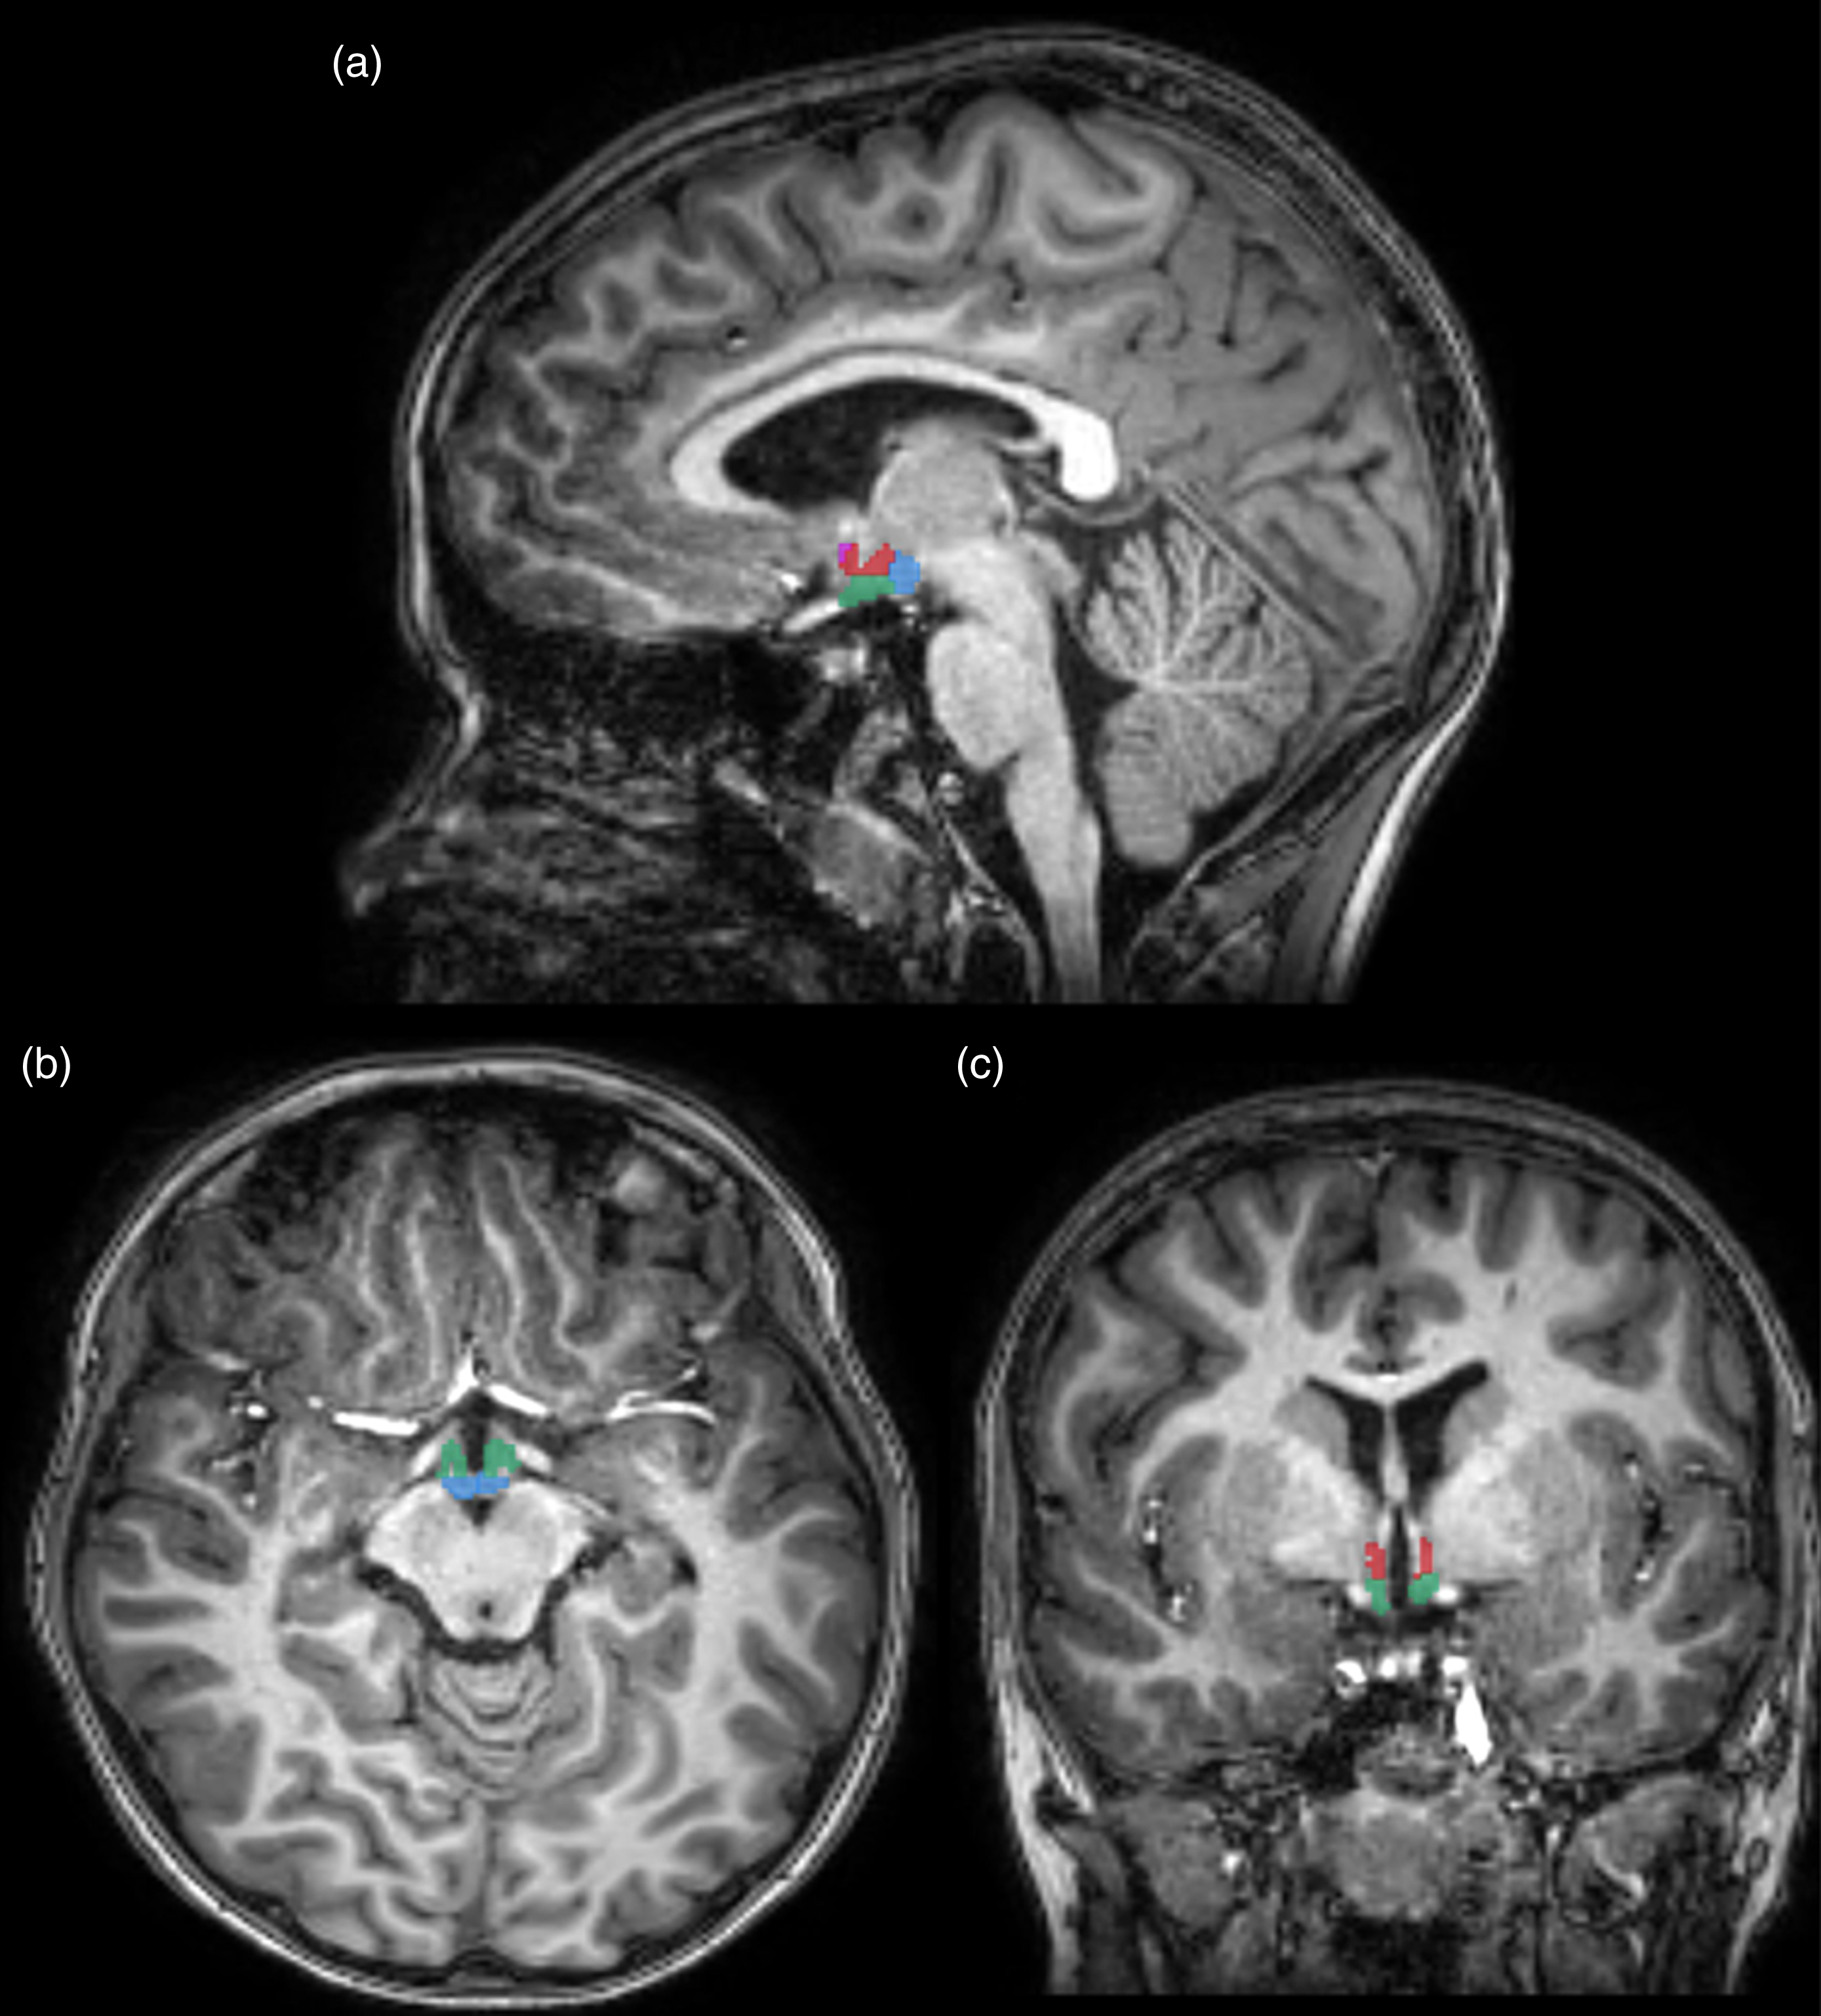

Figure 1. Example of automatically segmented hypothalamus in (a) sagittal, (b) axial and (c) coronal views. Pink circle = Anterior superior. Orange circle = Anterior inferior. Red circle = Tubular Superior. Green circle = Tubular Inferior. Blue circle = Posterior.